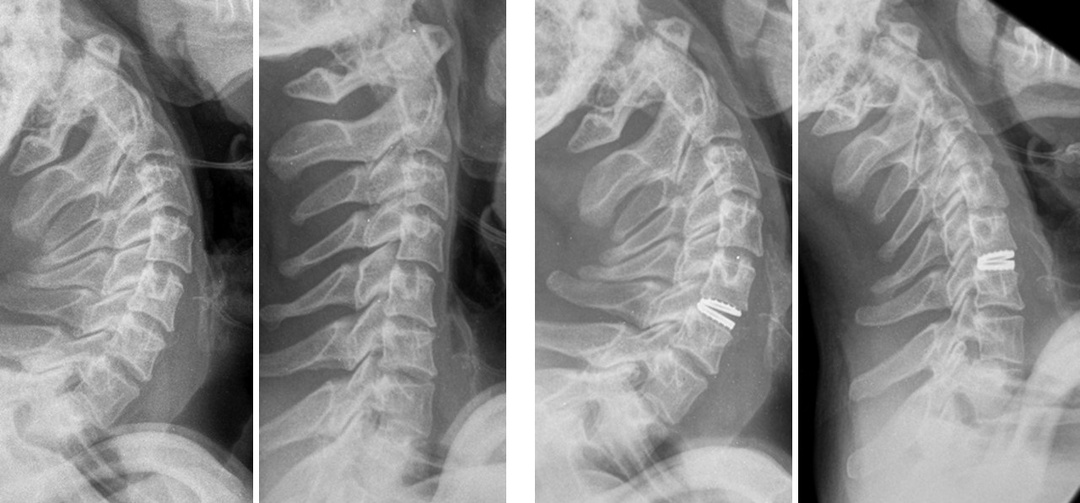

Пациент: 32 года, занимается тяжелым физическим трудом. Жалобы: более года мучили постоянные боли в шее, которые временно уменьшались только в положении лёжа. Диагностика:

Дегенеративное заболевание межпозвонкового диска с нестабильностью сегмента.

Консервативное лечение (медикаменты, блокады) не дало результата. Решение:

Эндопротезирование межпозвонкового диска — современная альтернатива спондилодезу, которая сохраняет подвижность позвоночника и снижает нагрузку на соседние сегменты. Результат:

Уже через 2 месяца после операции пациент полностью восстановился.

Вернулся к работе без ограничений. Помните: хроническая боль в шее или спине — не приговор! Современные методы лечения помогают вернуть качество жизни даже в сложных случаях.